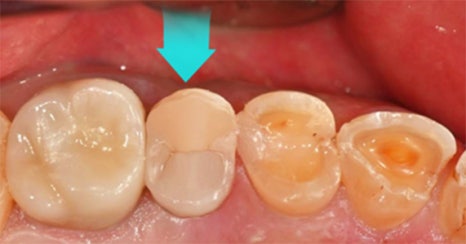

하루네이트는 바쁜 일상에서도

자신 있는 미소를 완성할 수 있는

하루플란트치과의 당일 라미네이트 치료입니다.

특히 물리적 거리상 여러 번 내원하기 어려운 분

또는 불편한 임시 치아를

피하고 싶은 분께 이상적입니다.

하루네이트의 당일 제작은 전문적인 기술과

첨단 장비를 갖춘 자체 기공소에서 이루어집니다.

숙련된 기공사의 세심한 작업과

지루하게게 발생하는 대기 시간을

최소화하기 위한 배려가 결합되어,

환자에게 최상의 결과를 제공합니다.